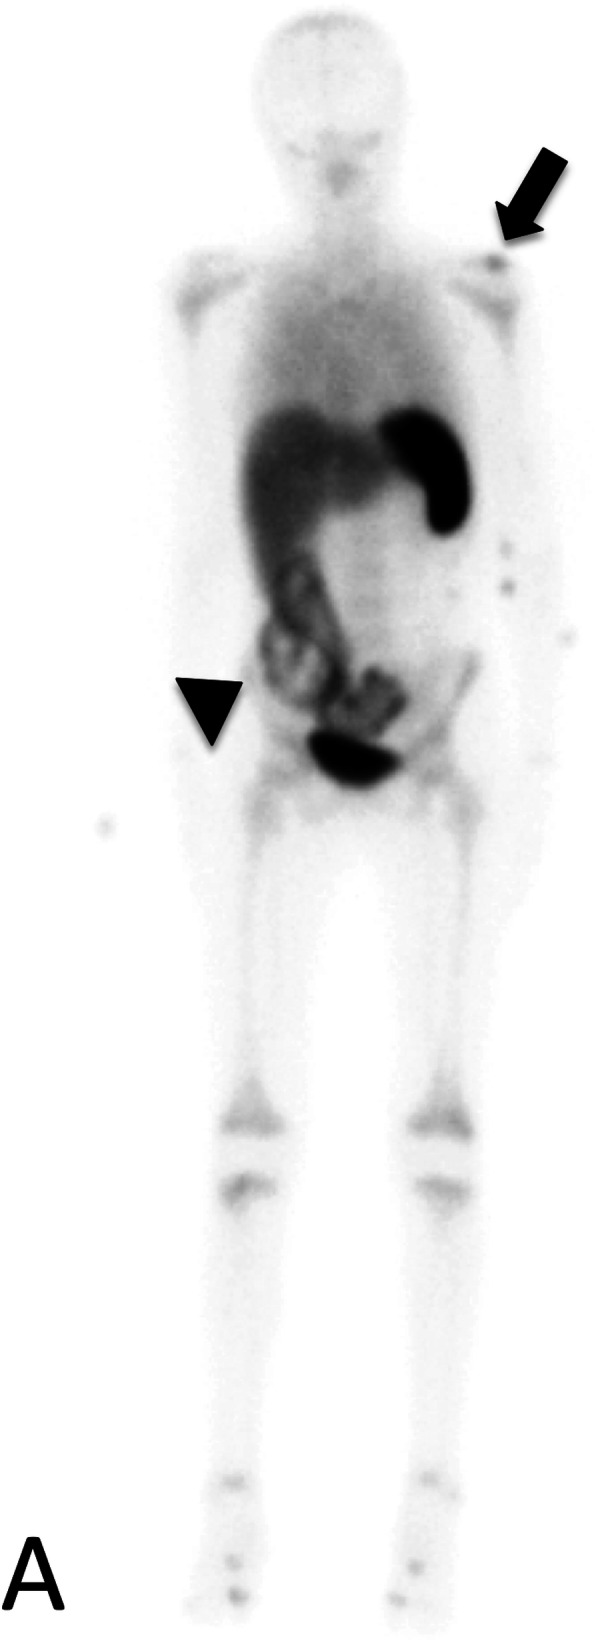

Fig. 2.

Nuclear Infection Imaging: 99 m Tc Ceretec WBC scan demonstrates abnormal focal radiotracer uptake at the left shoulder on delayed whole-body imaging (black arrow). Abnormal focal radiotracer uptake is also seen in the bowel of the right lower quadrant and pelvis, consistent with the patient’s history of ulcerative colitis (black arrowhead)